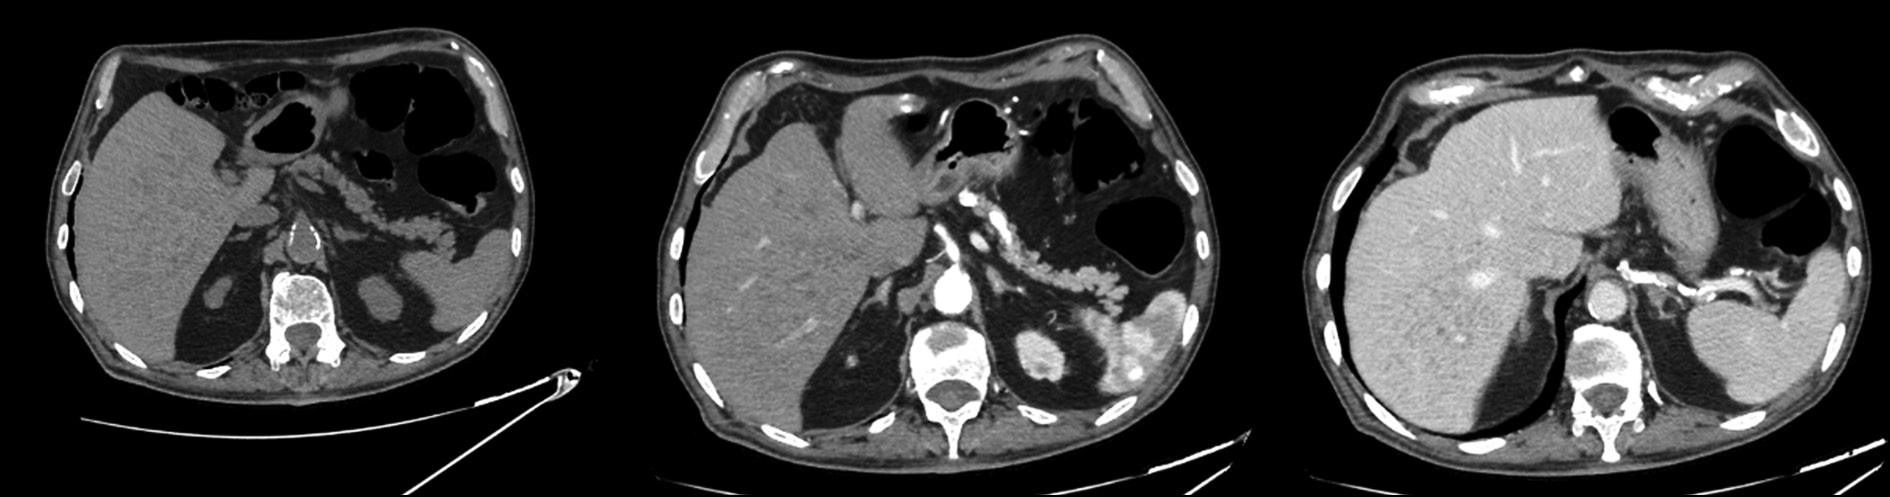

The patient presented at the hospital for a computed tomography scan and an abdominal magnetic resonance imaging recommended by his general practitioner to assess the biliary tree (magnetic resonance cholangiopancreatography), owing to persistent abdominal pain. The patient had never undergone an abdominal magnetic resonance imaging previously; hence, the discovery of hepatic lesions was incidental and unexpected.

Magnetic resonance imaging revealed multiple benign lesions in both the hepatic lobes comparable to the Von Meyenburg complex. These lesions are multiple hamartomas and behave differently in all magnetic resonance imaging sequences.

Images acquired with different magnetic resonance imaging sequences were carefully examined. Multiple lesions were found scattered throughout the liver; however, the lesions were benign and consistent with the diagnosis of multiple biliary hamartomas.